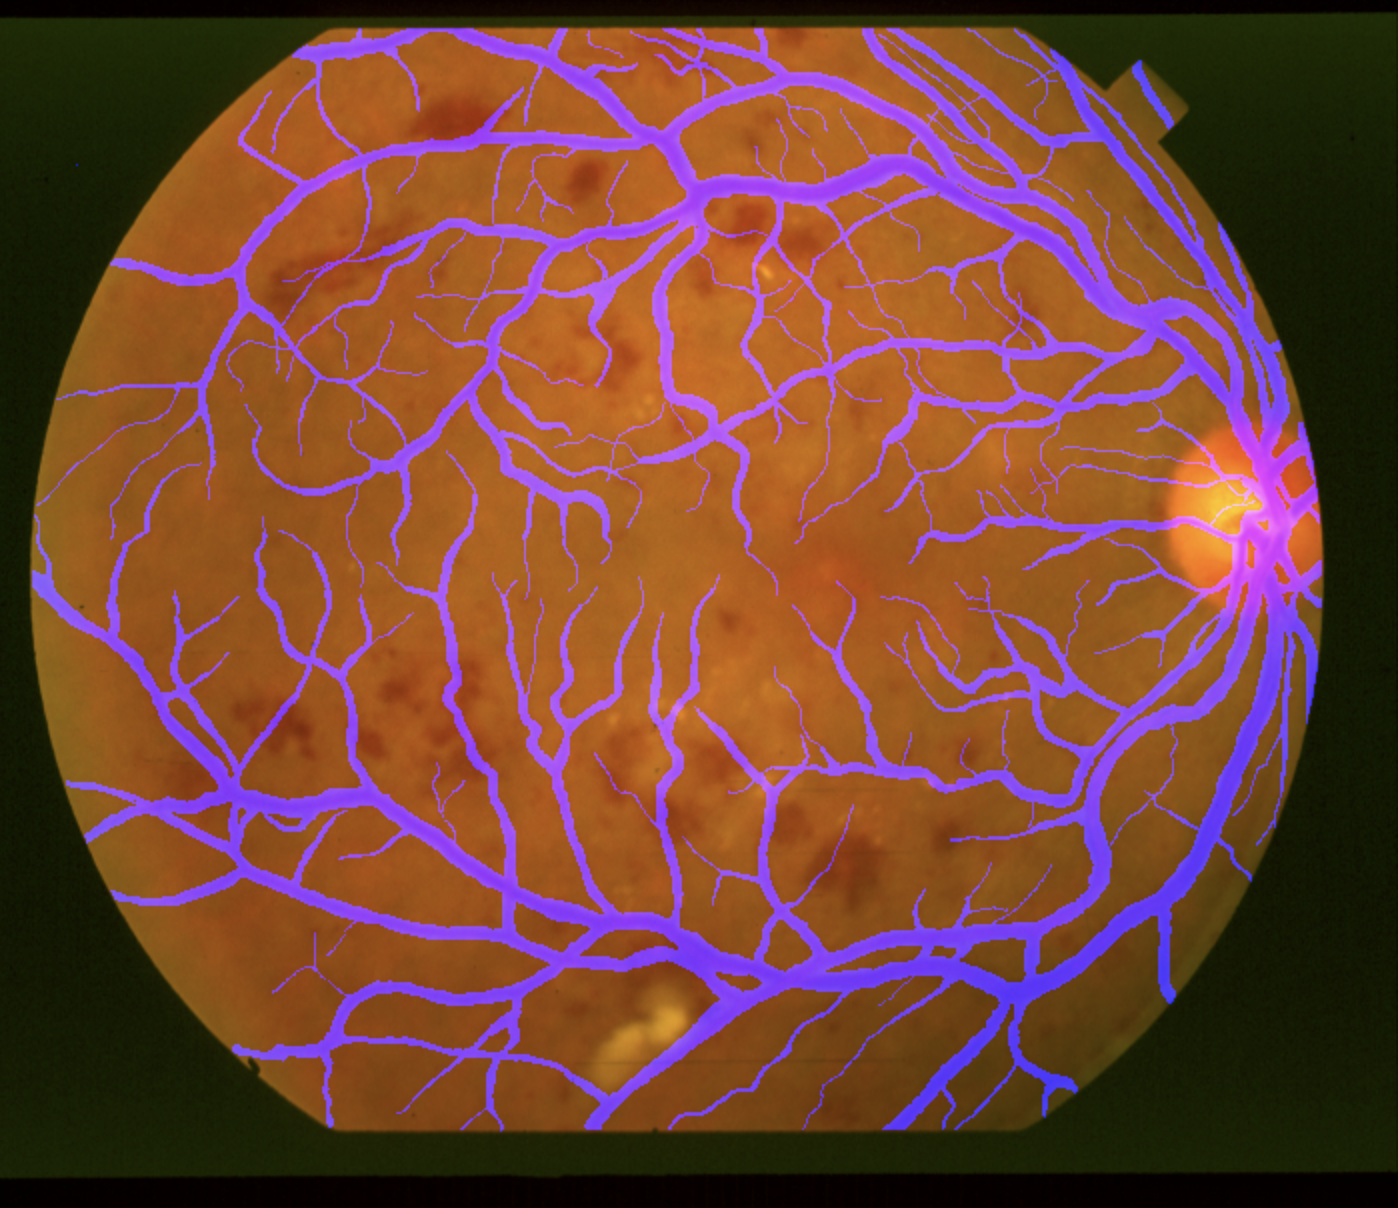

拿到的图片一般都是以下这样的

我拿到时,总共只有60张,可以说是少的可怜了,我试过直接用60张图片做训练,完全不行,train_loss都达到0.3,预测的图片黑的一片,可以肯定需要做数据增强了,由于对原图进行数据增强的时候,需要同时修改label的图片,我们可以把label的第1通道作为原图的第3通道,得到新的merge图

最后放一张实际预测的效果图,这个预测的准确度还是挺高的